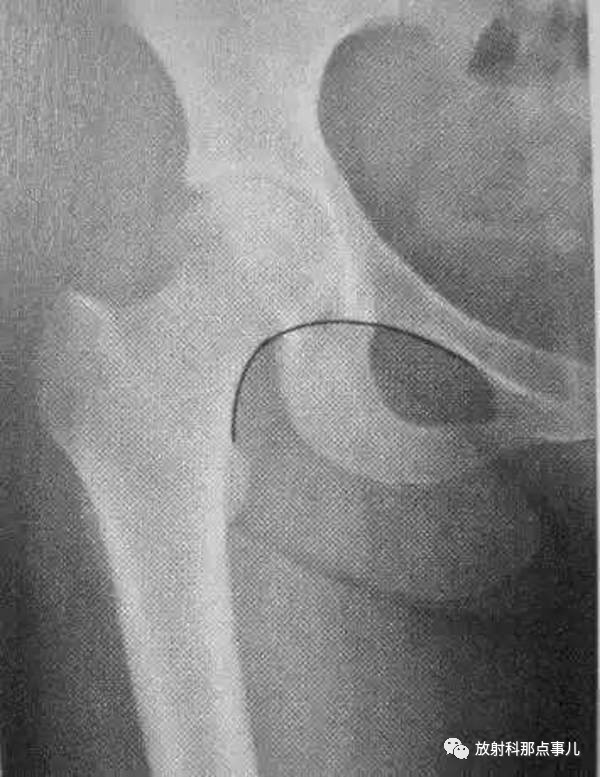

股骨髋臼撞击症骨科医生应该了解的x线表现

股骨颈外缘连线所形成的弧线,能够反映股骨头与髋臼的关系及髋臼上缘